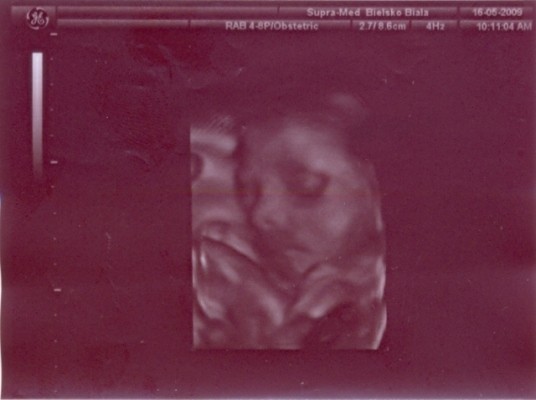

Mewa mój ma rzadko czkawkę tak z raz dwa razy w tygodniu....

to moja druga ciąza ale jakos niepamietam czy w pierwszej to miałam... pare razy na dzien twardnieje mi brzuszek tak na chwilke i puszcza.... dostałam na to leki feneterol biore juz 2tygodnie ale jakos niewidze poprawy coprawda lekarz powiedzial ze to tez moga byc naturalne twardnienia ktore nie sa niebezpieczne ale mowi ze lepiej dmuchac na zimne i zebym brała te leki....